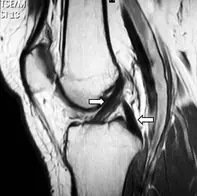

Blocage meniscal

Entorse de genou

Rupture du tendon quadricipital